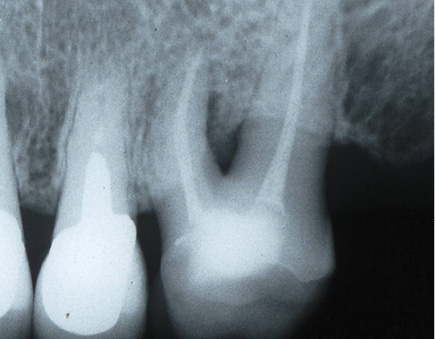

At the time of the examination, 10 (90.9%) ECs were in function in 10 patients. One EC had been lost after 12 years and 9 months due to periodontal disease in tooth #26. No restoration had loosened. Neither secondary caries nor radiographic failures were observed in the 10 PETT in function (Figs. 1a,1d; 2c; 3c,3d; 4c).

Fig. 1a Initial state in tooth #26. Buccal-Distal root must be resected.

Fig. 1d X-ray control after 9 years.